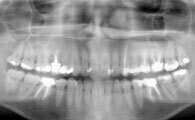

L'EXAMEN RADIOLOGIQUE PANORAMIQUE - DR OHANA - DENTISTE À COURBEVOIE 92400